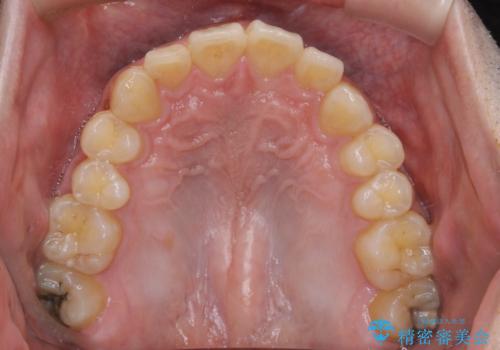

人生で初めてのクリーニングということもあり、プラークや歯石が大量に付いていました。それにより、歯茎の腫れもあり出血も多かったです。これから矯正をスタートしていくため、歯ブラシ指導を行いホームケアを頑張ってもらっています。